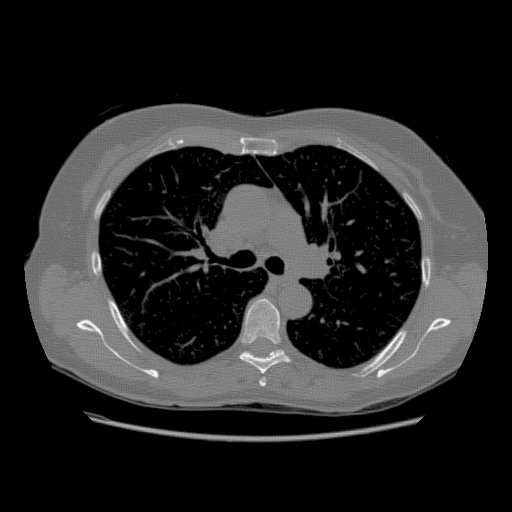

IV-A Effect of Residual Back Projection in Reconstruction

To demonstrate the efficacy of the RBP connection and show the details of the RBP-DIP’s reconstruction process, the procedure of a limited-angle CT reconstruction is shown in Fig.2. Its first row illustrates the results of reconstruction across different iterations, whereas the second row presents the respective inputs fed into the U-net, which are updated through the RBP connection. Here, the number of views is set to , uniformly distributed from to . This scenario presents a challenging limited-angle CT reconstruction problem.

In the first iteration, as depicted in Fig.2a, the input image undergoes an update via the RBP connection prior to being fed to the U-net. Thus, this input is the normalized first iteration output of the implemented IR algorithm (normalized back projection image in our case). The output appears completely randomized since the entire neural network is randomly initialized.

In the 10th and 20th iterations (Fig.2b and Fig.2c), the DIP property effectively expedites the recovery of the object over its support. Of note are lack of artifacts commonly caused by having missing views in the data. The input images highlight the region which can be relatively accurately reconstructed by conventional IR methods. This can be used to guide the model in the later iteration. In our experiment, the model capitalizes on the input images more when reconstructing the upper-left and lower-right segments of the image, while relying predominantly on the DIP property for the reconstruction of the upper-right and lower-left parts.

In the 2000th iteration, as depicted in Fig.2d, the reconstruction result becomes relatively artifact-free. At this stage, the network input primarily emphasizes the edges to help the method improve the supporting area. Moreover, the RBP connection can rectify artifacts specific to convolutional neural networks. Evidence of this can be observed in the second row of Fig.2c, Fig.2d, and Fig.2e, which display distinct horizontal and vertical patterns. These patterns are mainly caused by the convolution operation in the U-net. In other words, the DIP and RBP parts of the proposed framework are able to mutually rectify each other’s errors. Consequently, a high-quality reconstruction result is attainable, as shown in Fig.2e.

(a) 1st Iteration

(b) 10th Iteration

(c) 20th Iteration

(d) 2000th Iteration

(e) 10000th Iteration